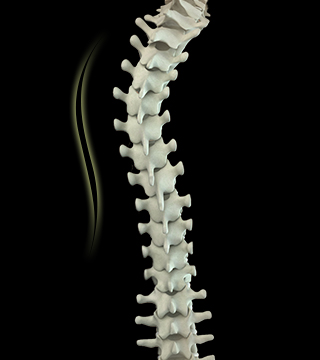

척추가 S자 또는 C자 형태로 휘어진 상태의 질환으로 좌우 어깨 높이가 다르거나 등, 허리의 한쪽이 다른 쪽보다 더 튀어 나온 체형의 이상이 발견됩니다.

앞이나 옆에서 전체 척추의 배열을 보았을 때 척추의 곡선이 과도하게 휘어진 증상을 척추측만증이라 합니다.